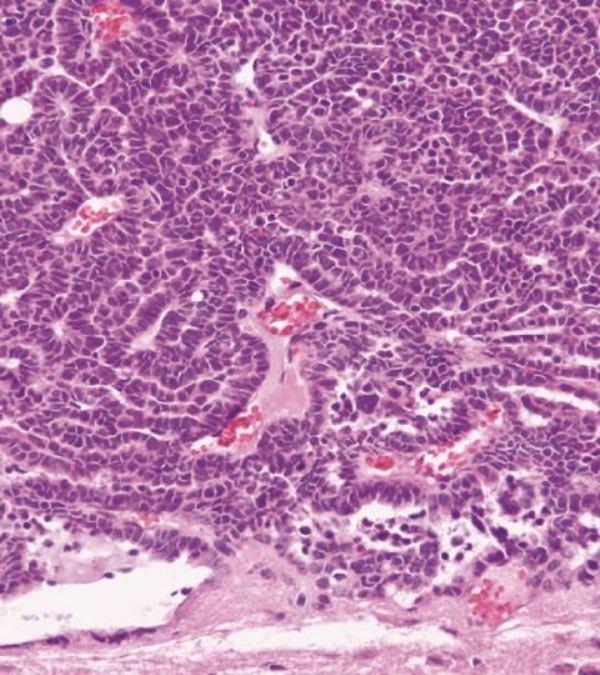

CPC develops in cells that line the fluid-filled ventricles in the brain and produce cerebrospinal fluid. When researchers introduced each of the 21 genes into mouse choroid plexus cells in the laboratory, only Taf12, Nfyc and Rad54l led to changes associated with CPC, including cell proliferation. Researchers also showed that all three genes were required to initiate and sustain the tumors in mice.